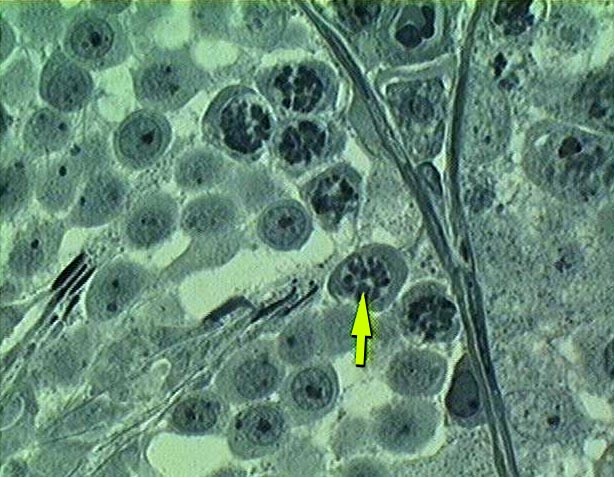

SEMINIFEROUS TUBULE OF TESTIS

Σπερματικό σωληνάριο όρχεος σε μεγάλη μεγέθυνση χρωματισμένο με σιδηρούχο αιματοξυλίνη. Βαθυχρωματικά χρωματοσώματα (βέλος) σε διάφορα στάδια συμπύκνωσης παρατηρούνται σε μερικά κύτταρα. Η συμπυκνωμένη χρωματίνη  στις κεφαλές των σπερματίδων και τα πυρήνια των μη διαιρούμενων κυττάρων χρωματίζονται επίσης μαύρα με τη σιδηρούχο αιματοξυλίνη.